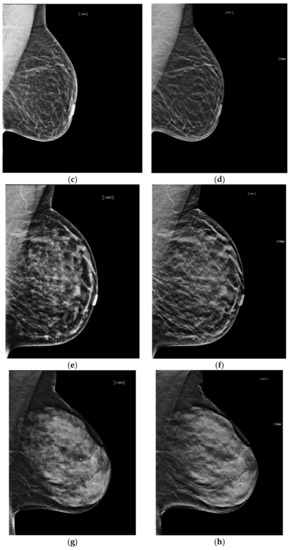

The reconstruction algorithm’s enhancement of line structures can also emphasize the appearance of architectural distortions (AD). Taken together with the ability of tomosynthesis to clear away superimposed tissue, s2D+DBT can permit confident identification of subtle cancers presenting as AD. (Figure 3).

Figure 3.

Architectural Distortion (circled in black) detected on screening mammogram with synthesized mammography and confirmed on tomosynthesis images (slices shown here), permitting confident Breast Imaging Reporting and Data System (BIRADS) 0 assessment. After diagnostic work-up and biopsy, pathology confirmed well-differentiated invasive ductal carcinoma, ER/PR+, Her2-, with grade 1 ductal carcinoma in situ. (a) s2D CC (b) DBT slice CC (c) s2D mediolateral oblique (d) DBT slice mediolateral oblique.

Giess et al. showed architectural distortions were significantly more conspicuous on synthesized mammography compared to FFDM (p < 0.001) [39]. Indeed, Mariscotti et al. found poor concordance in classification of AD between s2D and 2D FFDM (κ = 0.36), with six malignant ADs missed on 2D FFDM [33]. As s2D is derived from the DBT dataset, it may retain more information on tissue structure from the multiple projection images compared to 2D FFDM, emphasizing mammographic findings like AD.

Freer et al. reported no significant change in recall rates for AD with synthesized mammography [31]. This may reflect that AD characterization is best defined by tomosynthesis images, rather than by 2D or synthesized 2D.

It is important to note that normal ligaments may also be enhanced and present as possible distortions. As with calcifications, confirmation in both planes and with tomosynthesis can avoid false positive recalls. Careful diagnostic work-up and wariness of distortions that “spot away” remains prudent, given the high probability of malignancy of ADs. Additional studies could explore whether use of s2D increases detection of benign radial scars/complex sclerosing lesions, which may also present as AD.